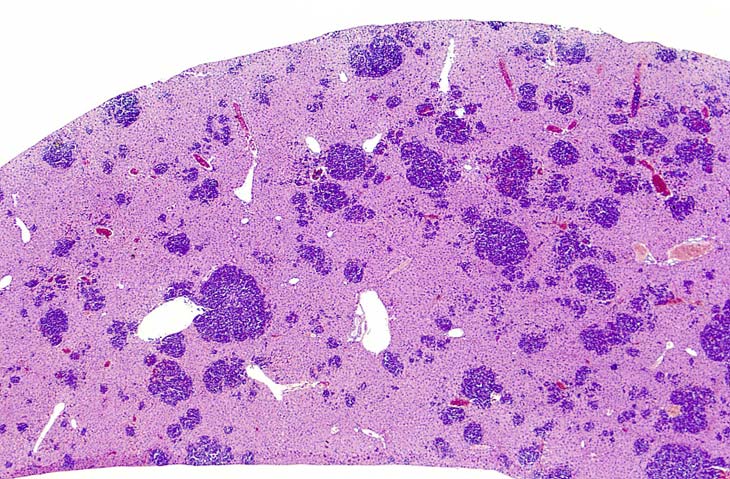

Erythroleukemia is a spontaneous hematopoietic neoplasm of Tg.AC mice characterized by marked hepatomegaly. The affected liver is infiltrated by metarubricytes and less differentiated erythroid precursors.

Low magnification of erythroleukemic infiltrates in the liver.

Examples of erythroleukemia in a Tg.AC mouse.